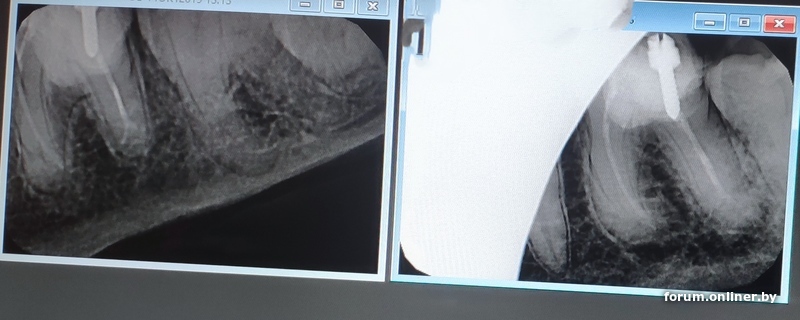

Всем привет.Подскажите кто перелечивал каналы или знает как должно быть. Пока имеется левая нижняя шестёрка. Залечили этот зуб летом 14 года точнее что от него осталось после несколько неудачных приёмов пищи отломалась большая половина зуба и в кабинете стоматолога добавилось ещё. В общем залечили кое как этот зуб и велели идти и ставить коронку но тогда я почитав о этих коронках какой геморрой меня ждёт и что функциональную функцию не несёт а посмотреть что там с зубом нету возможности под коронкой при поломке её потом не так просто снять решил что буду и дальше ходить с этим пнём. И в принципе устраивало но начиная с 18 года начались проблемы с зубами точнее мелкий кариес на правой стороне так как жевал в большой степени на правой. Обратился к другому стоматологу. Осмотрев все зубы сделали снимки некоторых зубов в частности этого проблемного. По снимку оказалось что предыдущий стоматолог не смог пройти канал до конца и запечатал какой то пастой это было в 19 году. И сейчас в 23 году что то стукнуло в голову что нужно ставить коронку на это зуб. Сделали опять снимок и оказалось что на корне этого зуба потемнение. Сам зуб сильно не беспокоит но врач сказала что при снижении иммунитета может дать знать. Поэтому и думаю что делать пытаться лечить этот зуб но где гарантия что удастся пройти канал до конца тем более в этой клинике нету микроскопа а как я читал что перелечивать каналы только под микроскопом значит нужно искать другого врача и клинику либо ждать пока не прижмёт удалять и ставить имплант зуб как никак жевательный

paf102:Поэтому и думаю что делать пытаться лечить этот зуб но где гарантия что удастся пройти канал до конца тем более в этой клинике нету микроскопа а как я читал что перелечивать каналы только под микроскопом

перелечивал каналы дважды, без микроскопа вполне себе, потом контроль снимком, что воспаление ушло

все зависит от врача

eddie_murphy:перелечивал каналы дважды, без микроскопа вполне себе, потом контроль снимком, что воспаление ушло

всё зависит от ваших зубов и организма), ибо физиологические возможности врача-человека без применения микроскопа - ограничены... и если там будут небольшие ответвления, то он вполне может их не увидеть... а узнаете вы про это лет через 10 например)